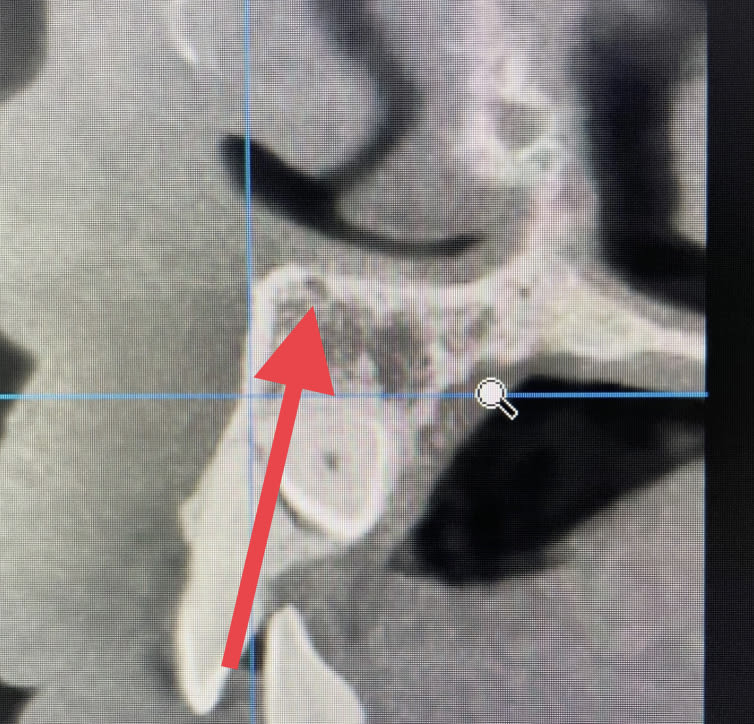

Dans le cas que tu as montré Gabzou le praticien a fait une effraction pulpaire…. Je te fais un petit zoom.

Dans ton cas Palpatine, je dis qu’il y a moyen de le faire sans effraction pulpaire. Foret initial et expansion (donc sans rogner d’avantage la dentine).

Moi je vois l'implant, 0.5 mm de zone forée vraiment sombre, puis 1mm de dentine moins dense, possiblement processus de résorption ou réactionnelle, puis zone vraiment sombre correspondant à l'endodonte. Cela dit, il peut y avoir eu une vraie perfo entre 2 plans de coupe de toute façon mais j'en doute, le patient ne rapportait pas de douleurs violentes suite à la pose de l'implant hors une contact direct aurait entrainé une pulpite. Il a pu oublier, mais en général on n'oublie pas une pulpite.

Tu vois ce que tu veux Gabzou :) hein …. Le mec est allé effleurer le nerf avec ses forêts. Faut pas s’étonner si derrière il y a eu des problèmes.